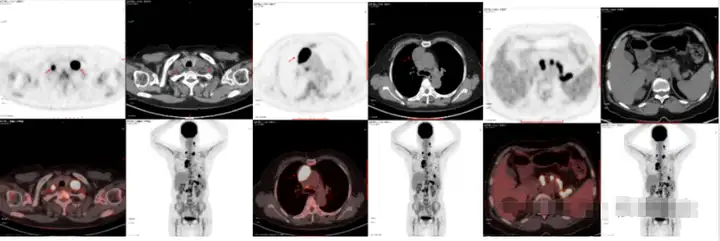

病例2

患者体检发现右肺结节,初步预行手术治疗。在术前进行了PET/CT检查。PET/CT检查除了发现右肺中叶结节糖代谢增高,还发现纵隔内及右侧锁骨上多个淋巴结增大伴代谢增高。行右侧锁骨上淋巴结穿刺,病理结果为转移性肺腺癌。按照TNM分期为IIIB期。虽然结节很小,但由于发生了远处淋巴结转移,手术治疗已不是最佳治疗手段。